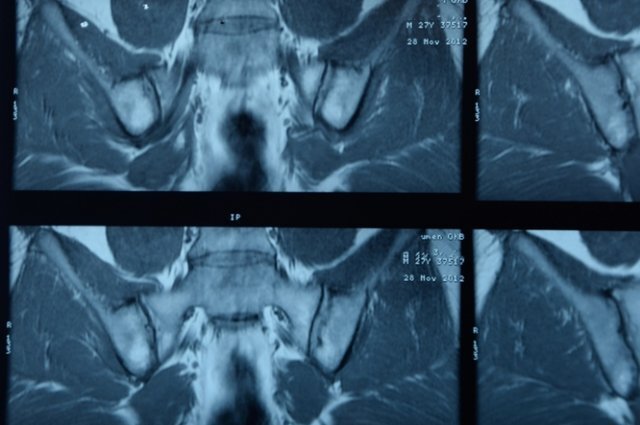

В зависимости от результатов рентгенологического исследования выделяют три стадии заболевания. На первой фиксируется наличие признаков воспаления крестцово-подвздошного сустава. На второй стадии появляются признаки его анкилоза (неподвижности). На третьей стадии диагностируются костные наросты в любом отделе позвоночника.